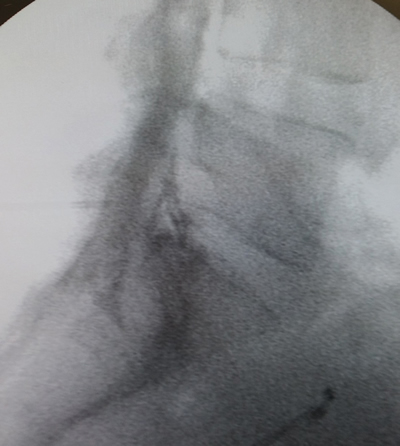

Los procedimientos fueron realizados en sala de operaciones, con anestesia local con lidocaína al 0,5 %, mediante abordaje interlaminar parasagital homolateral al dolor en los espacios L4-L5 o L5-S1, con aguja de Tuohy número 17 o 18, 3½ o 4¾ pulgadas según la complexión física del paciente, con identificación del espacio epidural mediante pérdida de resistencia con suero fisiológico. Se utilizó iopamiron como medio de contraste para visualizar el epidurograma (Figuras 1 y 2).

Fig. 2. Enfoque radiológico lateral de la inyección de contraste en el espacio epidural, durante una inyección epidural de esteroides mediante el abordaje interlaminar parasagital derecho a nivel del espacio L5-S1.